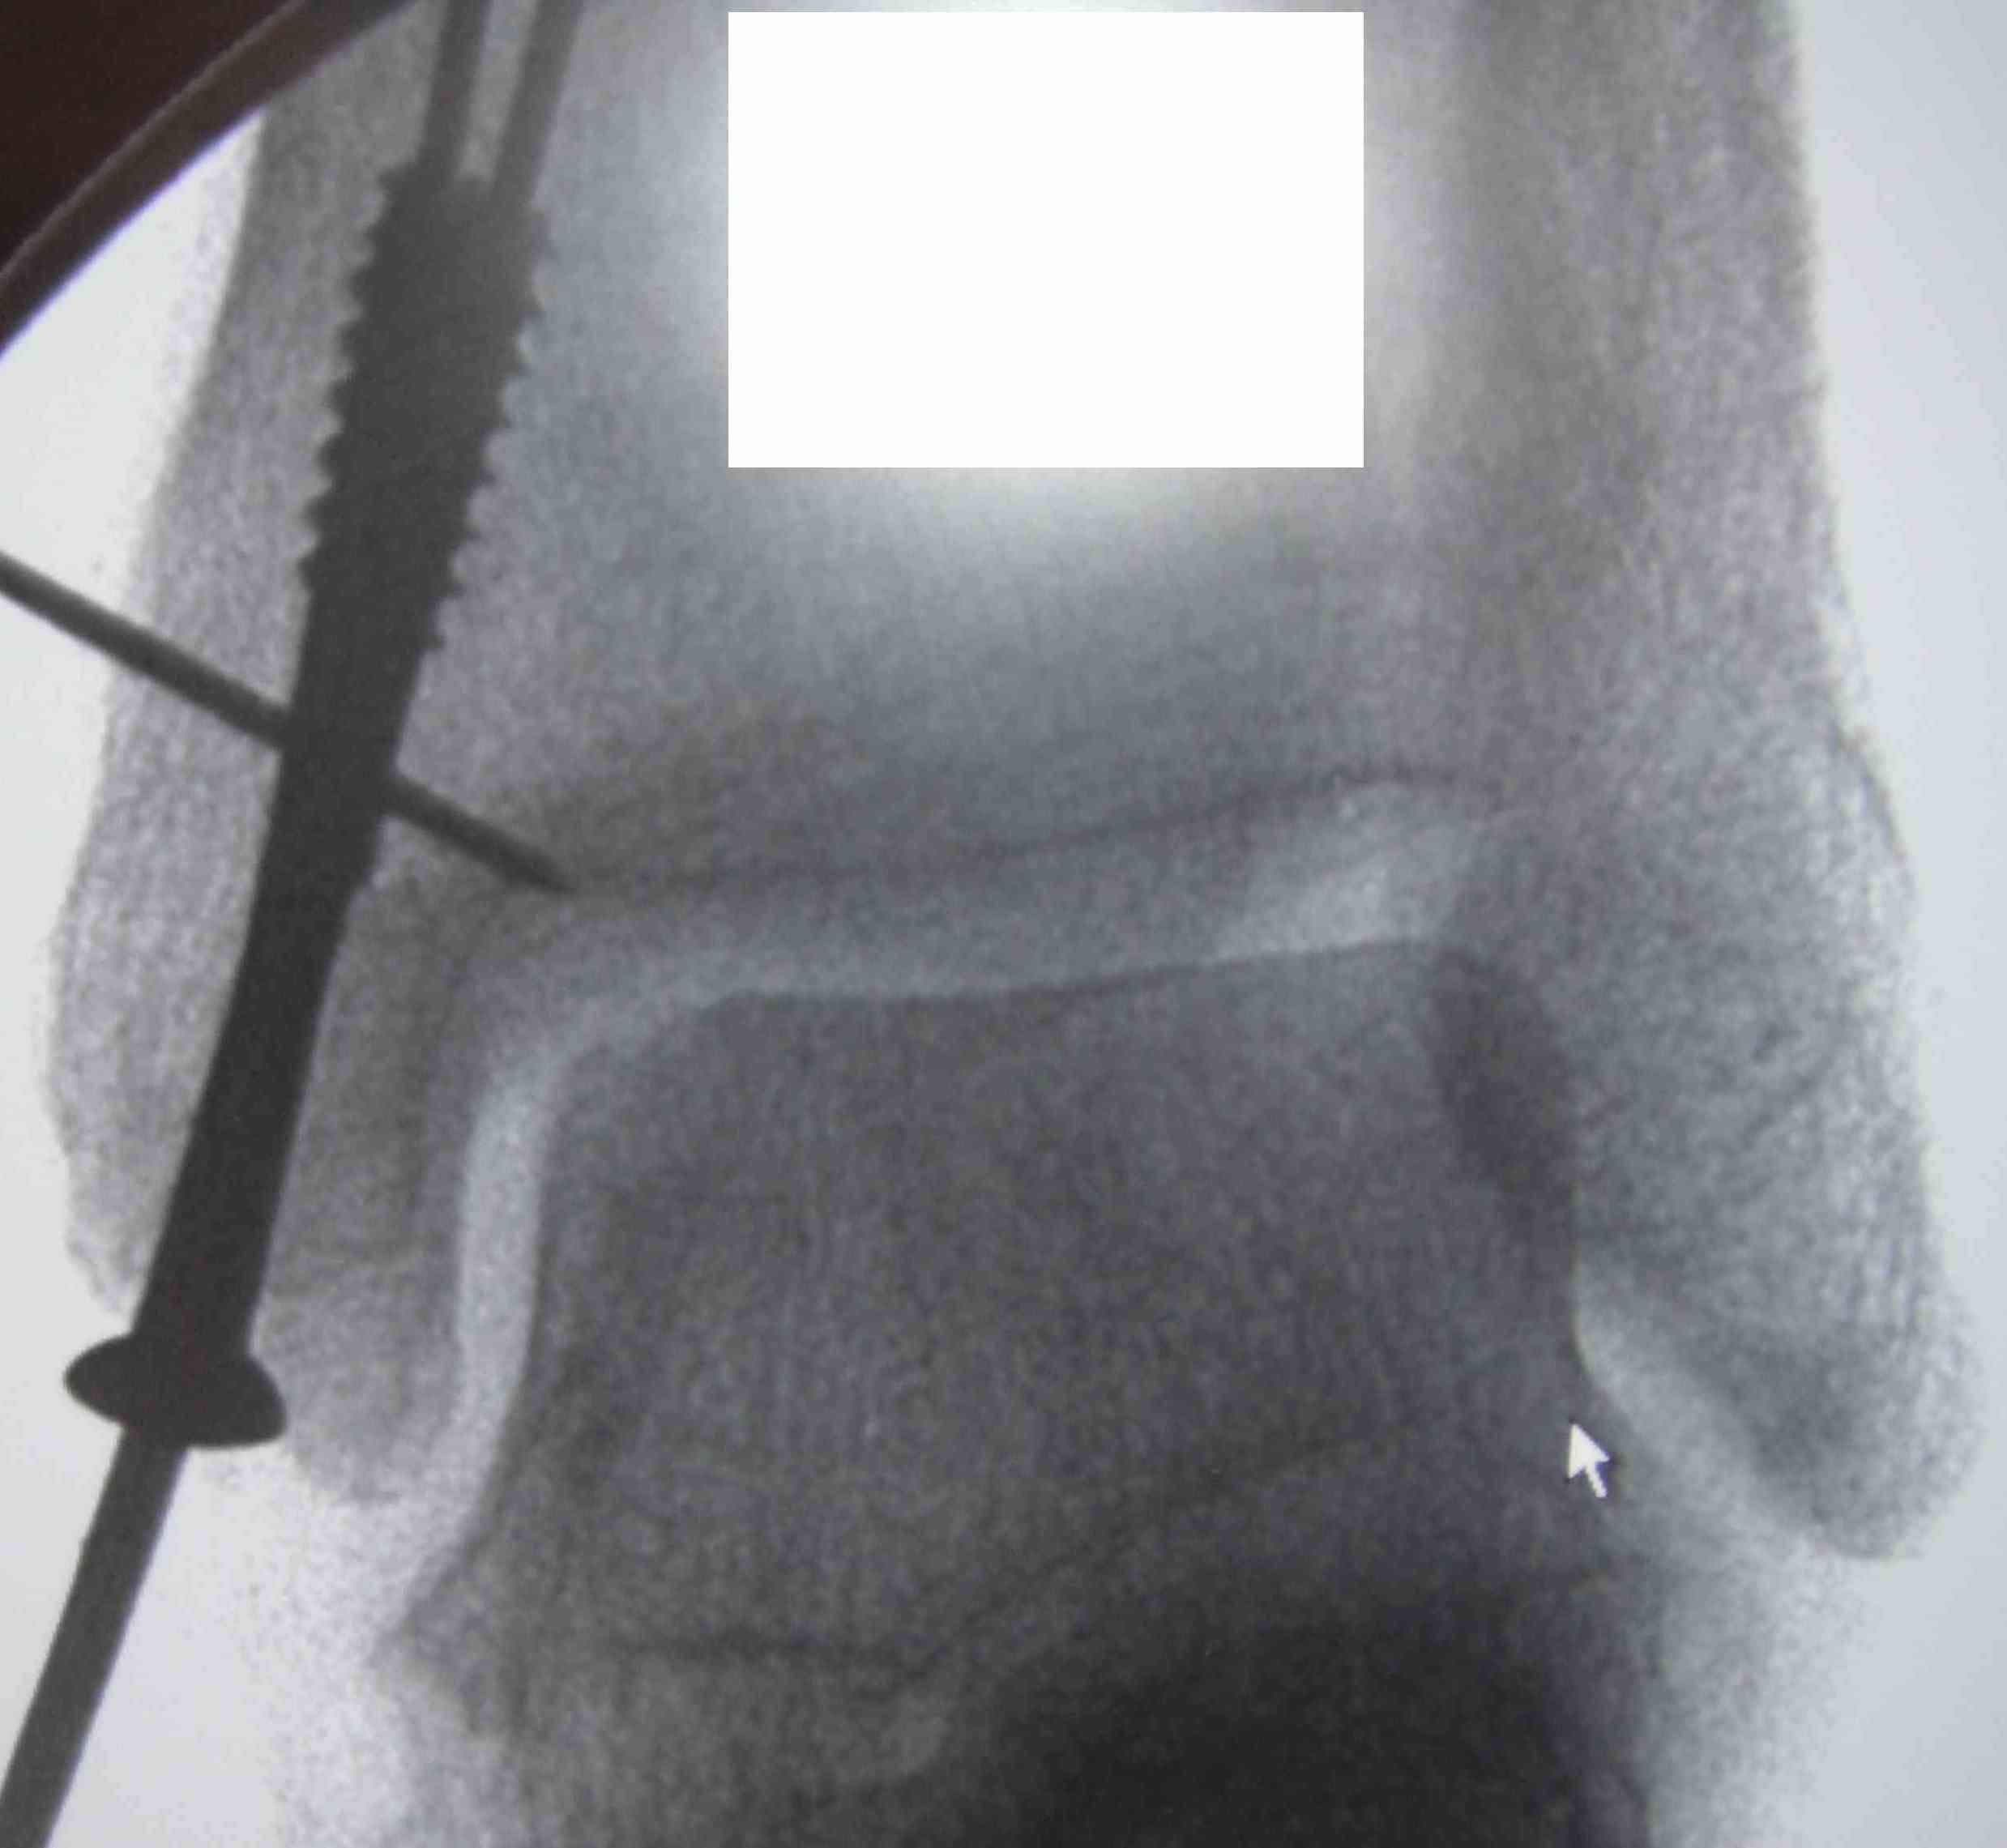

Medial Malleolar osteotomy

Predrill for screws

Arthrotomy / image guidance

Posterior homan to protect tibialis posterior

Initial osteotomy with saw / complete with osteotome